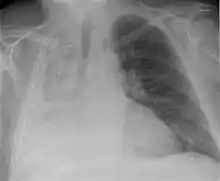

| Atelectasis of a person's right lung | |

Atelectasis is the partial collapse or closure of a lung resulting in reduced or absent gas exchange. It is usually unilateral, affecting part or all of one lung.[2] It is a condition where the alveoli are deflated down to little or no volume, as distinct from pulmonary consolidation, in which they are filled with liquid. It is often referred to informally as a collapsed lung, although more accurately it usually involves only a partial collapse, and that ambiguous term is also informally used for a fully collapsed lung caused by a pneumothorax.[1]

Clinically significant atelectasis is generally visible on chest X-ray; findings can include lung opacification and/or loss of lung volume. Post-surgical atelectasis will be bibasal in pattern. Chest CT or bronchoscopy may be necessary if the cause of atelectasis is not clinically apparent. Direct signs of atelectasis include displacement of interlobar fissures and mobile structures within the thorax, overinflation of the unaffected ipsilateral lobe or contralateral lung, and opacification of the collapsed lobe. In addition to clinically significant findings on chest X-rays, patients may present with indirect signs and symptoms such as elevation of the diaphragm, shifting of the trachea, heart and mediastinum; displacement of the hilus and shifting granulomas.[10]